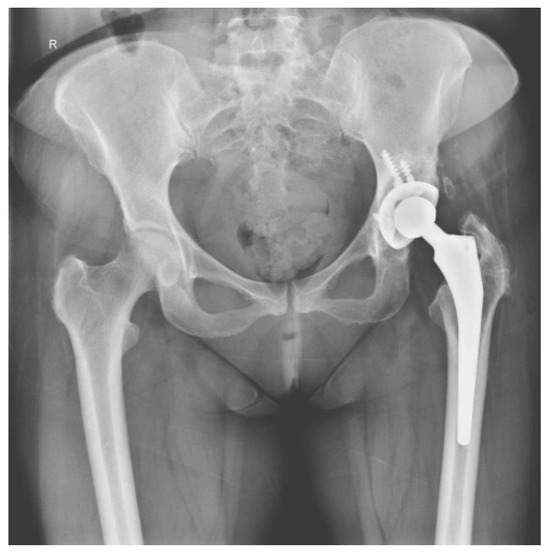

2.1. CASE 1